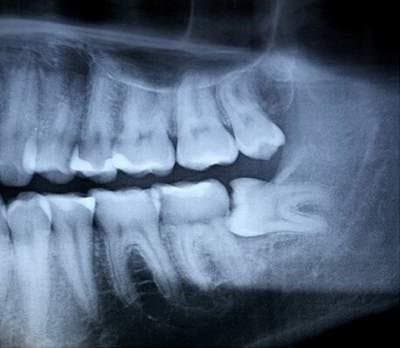

1.1. Răng khôn mọc ngầm 90 độ là như nào?

Răng khôn mọc lệch 90 độ là hiện tượng không hiếm gặp

Với trường hợp có đủ 32 chiếc răng, tức là 16 răng hàm trên và 16 răng hàm dưới, thì sẽ có 4 chiếc răng khôn. Tuy nhiên, thực tế nhiều người chỉ có 2 hoặc không có răng khôn nào. Theo thống kê, tỉ lệ răng khôn hàm dưới mọc lệch nguy hiểm nhiều hơn so với răng khôn hàm trên. Hiện nay, hàm của người trưởng thành thường chỉ có chỗ cho 28 chiếc răng, bao gồm 14 răng hàm trên và 14 răng hàm dưới.